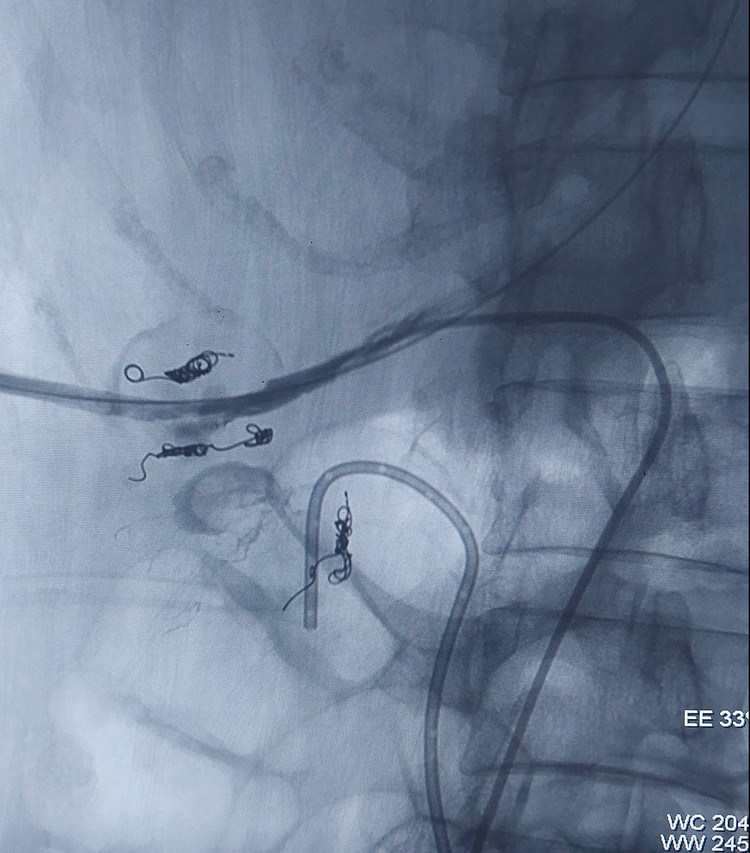

Rất may mắn, ca can thiệp đã thành công, đường hầm thận được đóng bởi surgicel – một vật liệu cầm máu dùng trong ngoại khoa.

![]() |

| Ca can thiệp Đường vào: động mạch đùi, tĩnh mạch đùi, xuyên qua da và đường hầm thận được đóng bởi surgicel – một vật liệu cầm máu dùng trong ngoại khoa. |